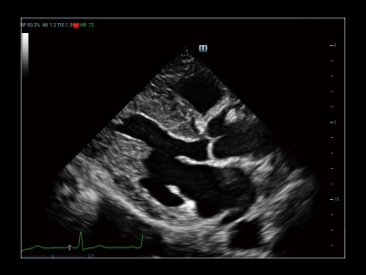

Potenciada por la tecnologĂa ZST+ y la ecografĂa de contraste mejorada (CEUS) basada en ondas planas, la HiFR CEUS permite que la ecografĂa de contraste mejorada ultrarrĂĄpida, para la visualizaciĂłn de la estructura vascular y perfusiĂłn en fase arterial, funcione como una herramienta complementaria de UWN+ (ultra-wideband nonlinear contrast imaging).

Caso HiFR CEUS: HNF de hĂgado

*No se recomienda aplicar HiFR CEUS en fase de retardo o en una regiĂłn de 10 cm de profundidad